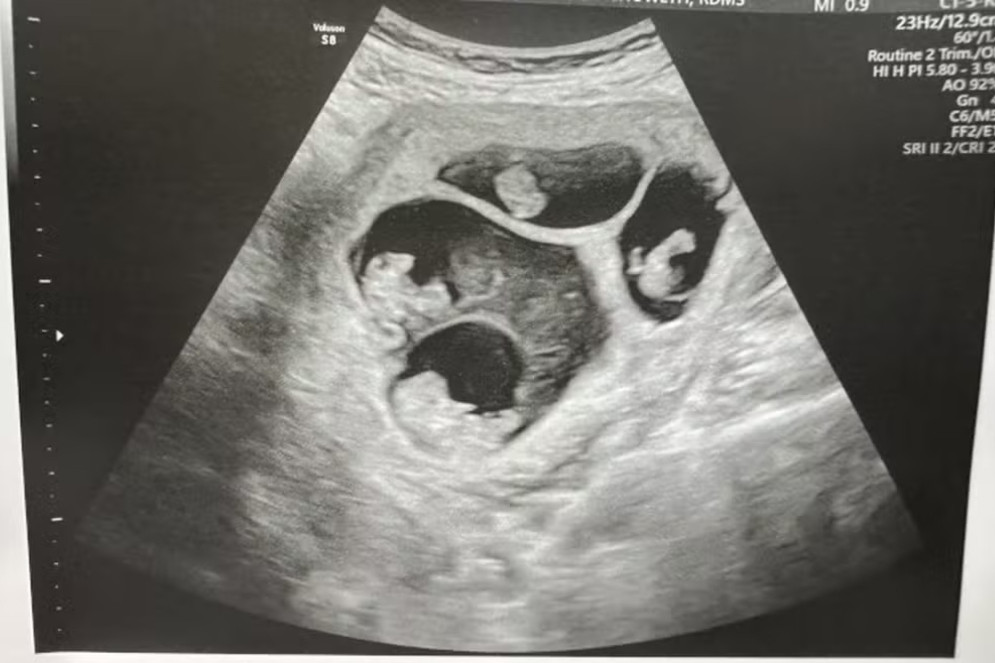

No ultrassom, foi possível enxergar os quadrigêmeos como três "manchas", duas pequenas e uma grande, que representam as placentas(Foto: Guinness World Records)

Foto: Guinness World Records No ultrassom, foi possível enxergar os quadrigêmeos como três "manchas", duas pequenas e uma grande, que representam as placentas